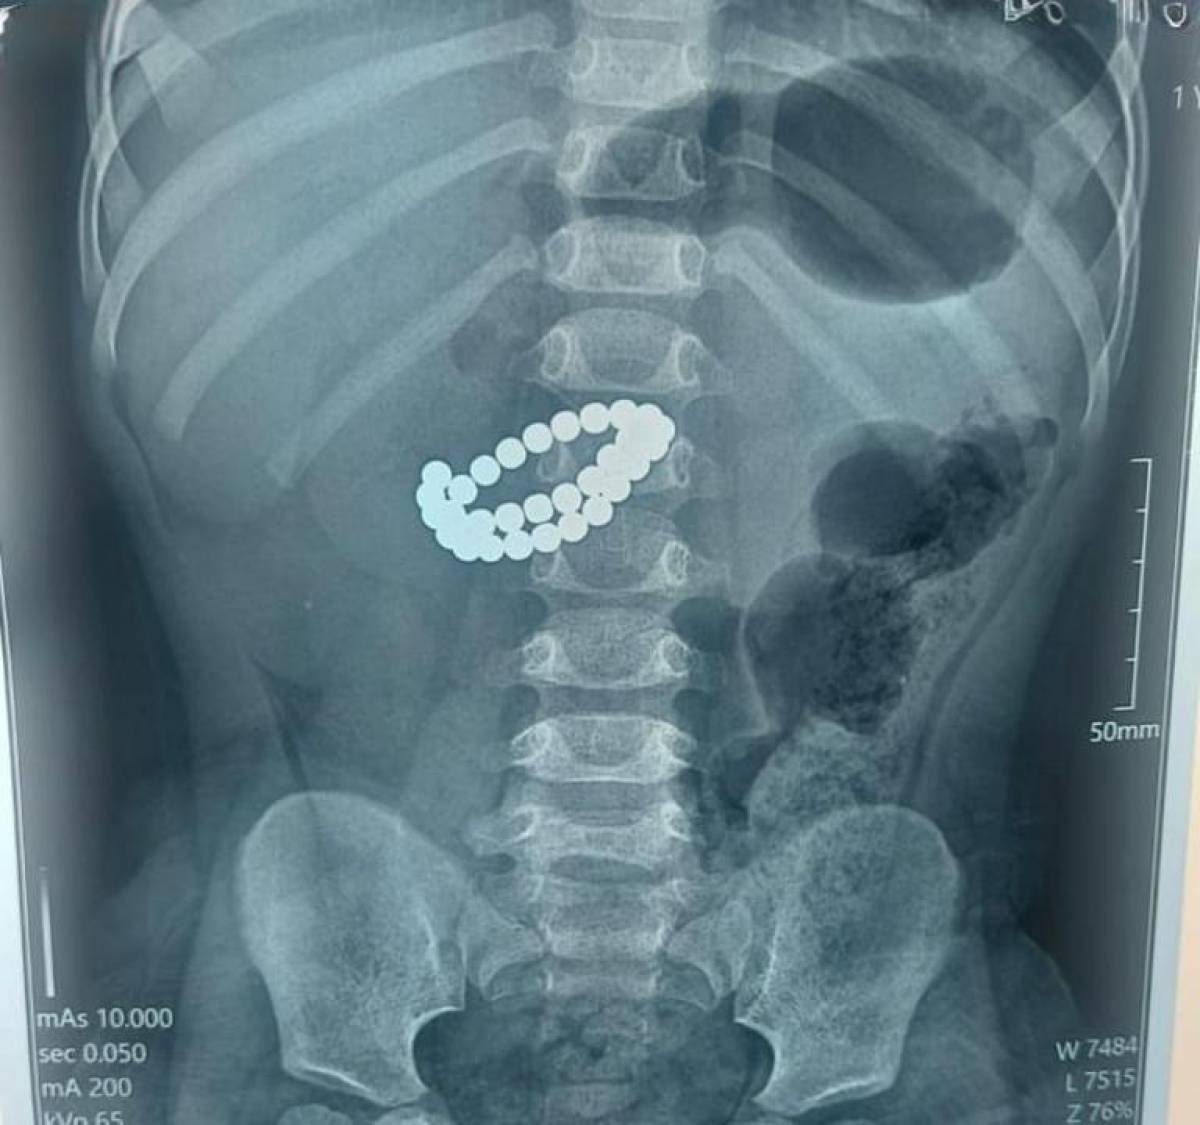

Алматының Балаларға шұғыл медициналық көмек көрсету орталығында 31 магнит жұтып қойған сәбиге шұғыл ота жасалды. Бұл туралы қалалық Қоғамдық денсаулық сақтау басқармасының өкілдері айтты, деп хабарлайды Arasha.kz.

Қабылдау бөліміне 1 жас 9 айлық бала өте ауыр жағдайда жеткізілген. Тексеру нәтижесінде дәрігерлер «ішектегі бөгде заттар — 31 магнит, жіңішке ішектің көптік тесілуі, жайылған нәжістік перитонит» диагнозын қойды.

Баланың өмірін сақтап қалудың жалғыз жолы – шұғыл хирургиялық ота жасау болды. Дәрігерлер ортаңғы лапаротомия жасап, құрсақ қуысы ағзаларына толық тексеру жүргізді. Ота барысында магниттер ішектен алынып, жіңішке ішектегі көптеген тесік тігілді, құрсақ қуысы тазартылып, дренаж орнатылды. Сонымен қатар ішекке трансаналдық интубация жасалды.